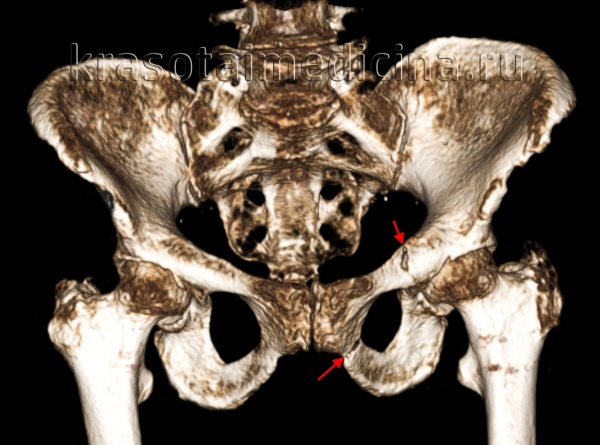

(Справа) На рисунке боковой проекции показан перелом обеих колонн с линиями переломов, отделяющими колонны и разрывающие возвышение седалищного нерва, а также изолирующие вертлужную впадину от крестца. Треугольное выпячивание изолированного перелома подвздошной кости с формирует признак шпоры, который можно визуализировать в области запирательного отверстия с помощью проекции Жюде.

• Симптом шпоры патогномоничен для переломов обеих колонн

(Слева) КТ, 3D реконструкция подвздошной проекции Жюде: определяется изолированный перелом крыла подвздошной кости (Дювернье) вследствие удара о дерево при катании на лыжах. Несмотря на распространение перелома в соседнюю губу вертлужной впадины, повреждение сустава отсутствует.